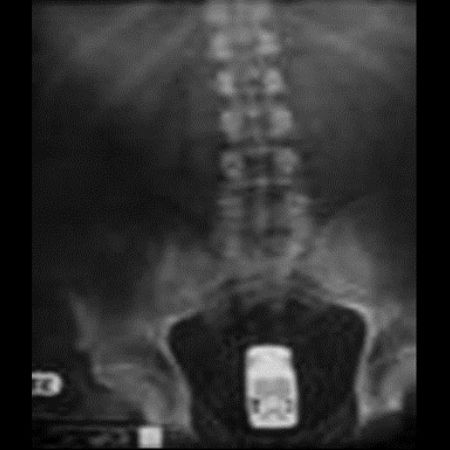

お尻は日本でもたまーに救急に来るで

肛門 異物

肛門に異物はよくあるらしい。やり過ぎると地主になってしまうので程ほどにね。

尻に異物が入る時はだいたい「転んだ拍子に」って言うけど医療関係者はそんな与太話は誰も信じてないだろうね。

ボトルとか瓶とかよくお尻に入れられたな